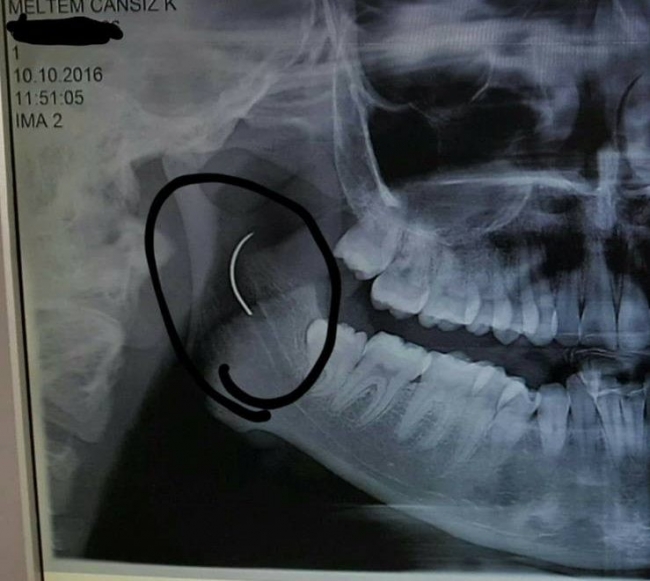

Boğazındaki iğneyle geçen 18 yılını anlatan Meltem Cansız, "3 yaşında geçirdiğim bademcik ameliyatında iğne boğazımda unutulmuş. Daha sonra iğneden dolayı 11 yıl sonra 14 yaşındayken kulak rahatsızlığım ortaya çıktı. Kafamın sağ tarafı ağrımaya başladı. Doktora gittik, hiçbir şey olmadığını söylediler. Sonrasında beni MR çekilmek üzere Akhisar'a yönlendirdi. Gecenin bir vakti MR'a girdim. Ancak bir türlü çekemediler. Benim üzerimde toka vs. metal bir şey olduğunu söylediler baktılar ancak bir şey yoktu. Üç yada dört defa MR'a girdim. Ancak bir türlü çekemediler. Sonra doktorumuz röntgene yönlendirdi. Röntgen görüntüsünde ameliyattan kalma bir çengelli iğnenin boğazımda olduğu görüldü. Bunun için beni Ege Üniversitesi'ne sevk ettiler. Burada doktorlar bu ameliyatı yapabileceklerini ancak riskinin çok olduğunu söylediler. Biz yine de kabul ettik. 1,5 saatlik operasyon geçirdim ancak iğneyi bulmadıklarını söylediler. 2 sene kadar araştırma yaptık. Birçok hastaneyle görüştük. Ancak ayağımda bir rahatsızlık meydana geldi. Ayağım için Ege Üniversitesi'ne gittik. Tekrardan beni ameliyat eden doktorumla görüştüm. 'Seni ben ameliyat ettim, tekrardan buna kalkışamam' dedi. MR'a da giremezsin dediler. 'Sen bununla yaşamayı öğren' en azından bunun için çabalama alınmaması daha iyi dediler. Ben daha genç bir kızım sonuçla bu iğneyle ömür boyu yaşayamazdım. Yaşanan bu olumsuzların ardından araştırmalarımız neticesinde en son İzmir'de özel bir hastaneye gittik. Oradaki doktorum Çağlar Çallı bey bana umut verdi. 'Bu iğneyi alacağız' dedi. İnancımı kaybetmedim, sonucun ne olacağını bilmeden girdim ben o ameliyata. Ölüm, felç olma riskim çok fazlaydı. 'Yaşayamayabilirsin' dediler, biz bile bile lades dedik. Sonucu da güzel oldu" dedi.

Ege Üniversitesi'ne gittiklerini belirten baba Cansız, iğnenin şah damarına çok yakın olduğunun söylendiğini belirterek şunları söyledi: "Doktorlar çok tehlikeli bir ameliyat olacağını yanlış ya da en ufak bir hatada kızımızın bir tarafının felç kalabileceğini veya hayatını kaybedebileceğini söylediler. Biz bu riski göze alarak ameliyata müsaade ettik. Fakat iğneyi görüldüğü yerde bulamadıklarını söyleyerek alamadılar. Sonra İzmir Çiğli'de özel bir hastanede denedik. Kendisine binlerce kez teşekkür. Allah razı olsun. Çocuğumun boğazındaki iğneyi aldı. Dünyalar bizim oldu."